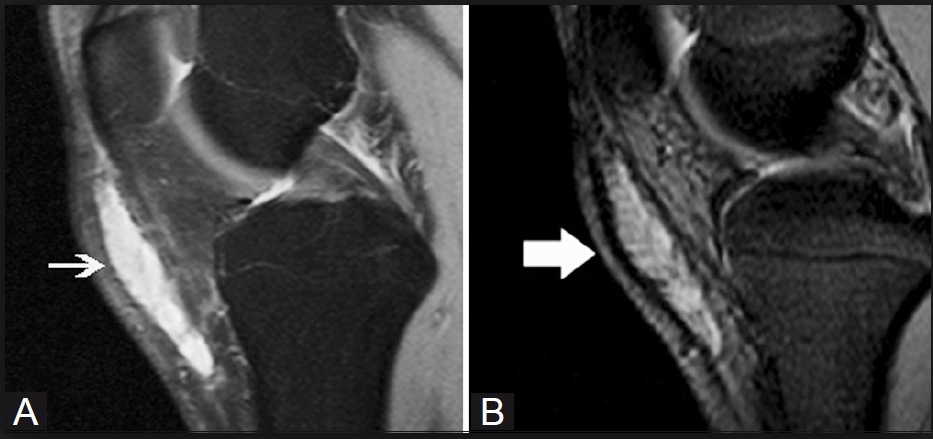

- Olecranon bursitis, "student's elbow", characterised by pain and swelling in the elbow

주두 점액낭염(olecranon bursitis)